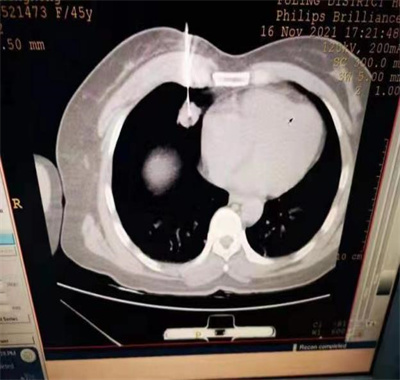

近日,涪陵区人民医院呼吸内科成功开展了一例CT引导下行经皮肺穿刺活检术。该术是借助CT扫描肺部定位病变部位,适用于:肺部结节或肿块性病变:经正规抗炎治疗或经一定时间观察后病变无变化或稍有增大时;肺内多发性结节,不能确定是原发或是转移性肿瘤,是多源性肿瘤,还是肺肿瘤的肺内转移;从影像学观察肺内为转移瘤,寻找原发灶提供线索;已知影像学诊断为肺恶性肿瘤,但需有组织学分型,以便为化疗、放疗或手术治疗提供依据。肺内其他病变:肺部炎症,穿刺活检为了取得病原学诊断。进而经皮肤将针穿入肺部病灶,获取病变组织的一项诊断新技术,此技术具有安全高效、创口小、痛苦小、诊断准确率高、费用低等特点。

患者张某肺部CT示多发结节,为进一步明确其性质,以便指导临床制定适宜的治疗方案,涪陵区人民医院呼吸内科周主任决定为张某行经皮肺穿刺活检术,在重庆人民医院周教授的指导,为患者进行经皮肺穿刺活检术,手术过程顺利,成功获取肺组织标本送病理科检查,术后,患者张某肺部无局部出血及气胸等并发症出现。